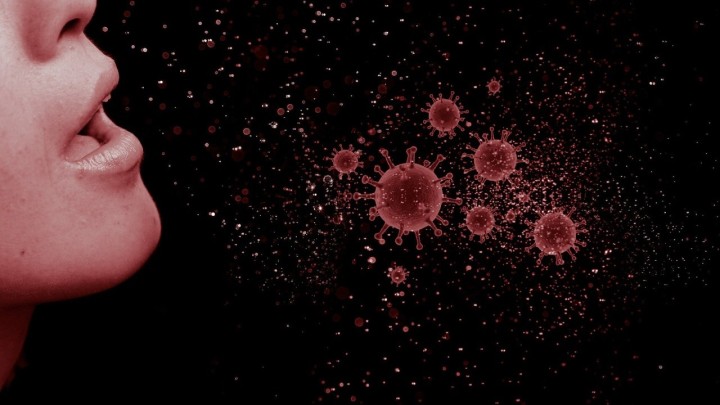

Istraživanje je potvrdilo: Vježbanje vas može zaštiti od COVID-a

Stariji, ako imate ovaj problem, mogli biste biti 'superširitelji' koronavirusa